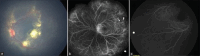

Rare pediatric retinal disorders present significant challenges in diagnosis and management due to their limited prevalence and diverse clinical manifestations. This paper provides a comprehensive review of select rare retinal disorders affecting the pediatric population, focussing a brief on their epidemiology, clinical characteristics, diagnostic modalities, and therapeutic interventions. Through a systematic examination of current literature and clinical case studies, this review aims to elucidate the distinct features and challenges associated with each disorder. Despite the rarity of these conditions, their impact on visual function and quality of life necessitates heightened awareness among clinicians and researchers to facilitate timely diagnosis, appropriate management, and improved outcomes for affected children as their visual systems are still developing. Furthermore, advancements in diagnostic modalities such as fundus fluorescein angiography, optical coherence tomography, electroretinography, and genetic testing are examined for their role in enhancing our understanding of rare pediatric retinal disorders and facilitating early intervention strategies. The literature selection for this article was conducted through PubMed, Google Scholar, and the Cochrane Library databases. A thorough systematic search was carried out for the concerned diseases. Relevant review articles, original research studies, case series, and reports were examined. Additionally, references from these sources were reviewed and included if they provided pertinent information on the topic. The search was not restricted by publication date.

Keywords: Coats disease; familial exudative vitreoretinopathy; incontinentia pigmenti; inherited diseases; pediatric retinal diseases; pediatric uveitis; persistent fetal vasculature; retinoschisis; shaken baby syndrome; sticklers; tumors.